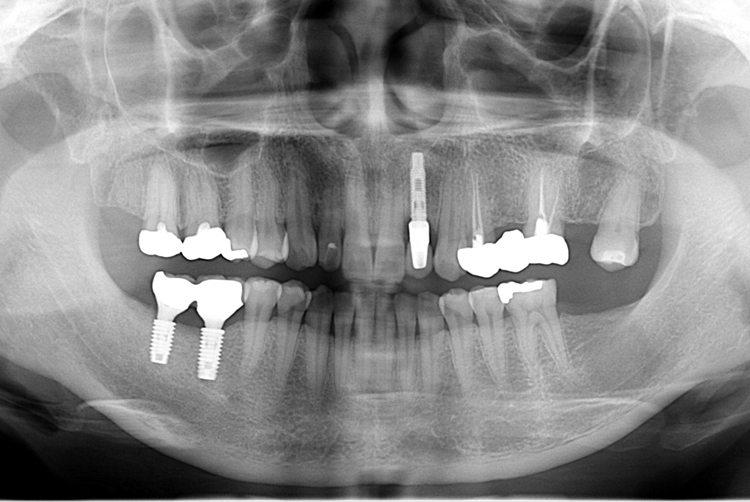

[임플란트] 앞니 임플란트

치료후 : 2018-08-09

세종치과는 많은 환자와 다양한 케이스를 바탕으로

항상 편안한 임플란트 수술을 제공하고자 노력하고,

오래동안 튼튼히 쓸 수 있는 임플란트 수술을 가장 큰 목표로 삼고 있습니다.